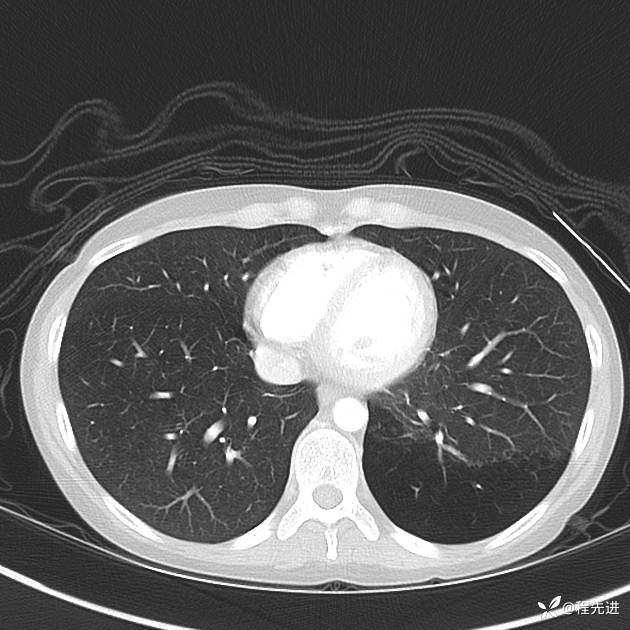

患者性别:女

患者年龄:25岁

简要病史:下胸部疼痛3天

CT增强: